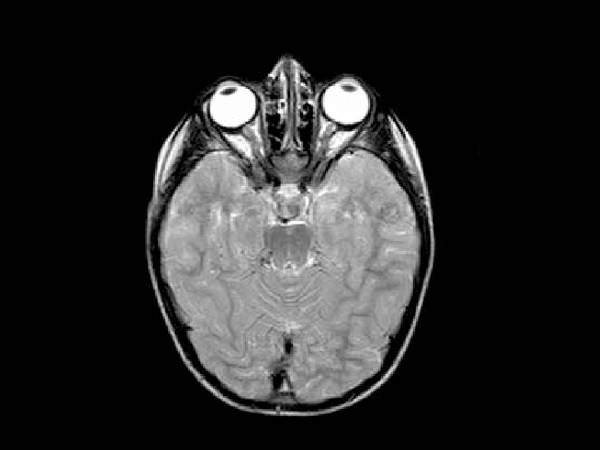

3. எம்ஆா்ஐ ஸ்கேன்

எம்ஆா்ஐ ஸ்கேனில் சக்தி வாய்ந்த மின் காந்த அலைகளைப் பயன்படுத்தி, கட்டிகளின் அளவு, அவை எந்தப் பகுதியில் இருக்கின்றன மற்றும் அந்த கட்டிகள் வேறு பாதிப்புகள் எதையும் ஏற்படுத்தி இருக்கின்றனவா போன்ற தகவல்களைக் கண்டறியலாம்.

கண்களின் சுற்றுவட்டப் பாதை மற்றும் எலும்பற்ற திசுக்களை மிகத் தெளிவாகவும், தரமாகவும் அதே நேரத்தில் 3 விதமான கோணங்களில் படமெடுக்கவும் எம்ஆா்ஐ ஸ்கேனைப் பயன்படுத்தலாம். எலும்பற்ற திசுக்களைப் படமெடுக்க சிடி ஸ்கேன் மட்டும் போதுமானது. எனினும் எம்ஆா்ஐ ஸ்கேன் எடுத்தும் பாிசோதனை செய்யலாம்.